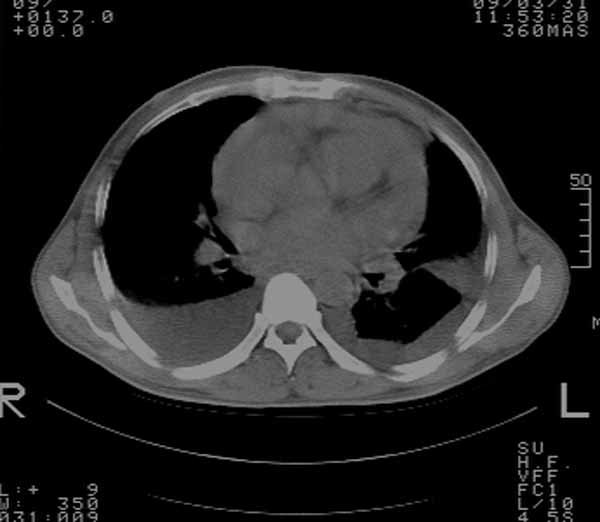

以下是引用余辉在2009-3-31 18:43:00的发言:[br]肺水肿,双侧心腔积液,心包积液,心影增大,疑似心衰

以下是引用wangyong1977在2009-3-31 20:46:00的发言:[br]肺水肿,双侧胸腔积液,心包积液,心影增大,疑似心衰 [br]

以下是引用宇宙ct在2009-3-31 18:57:00的发言:[br]肺水肿,双侧心腔积液,心包积液,心影增大,疑似心衰 [br] [br]